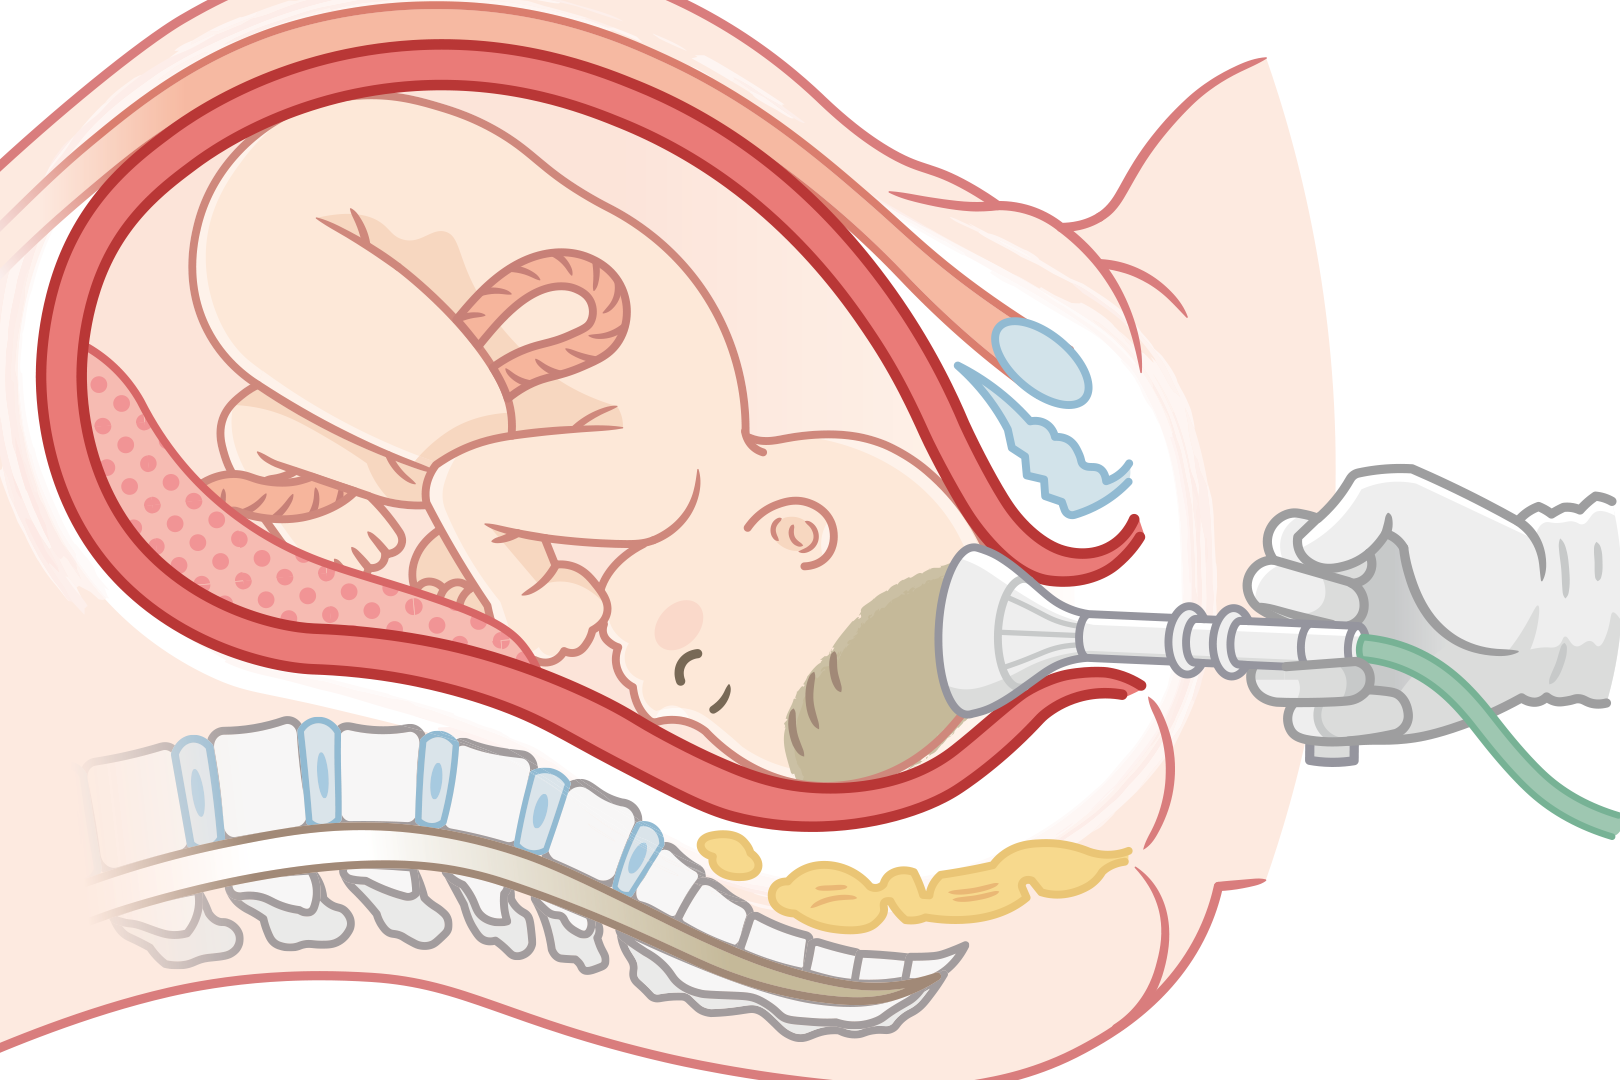

【吸引分娩は医療保険適用?】適用される場合の必要書類や手続き方法

異常分娩は保険適用?吸引分娩は?会陰切開、陣痛促進剤は対象?

正常分娩時の会陰切開、陣痛促進剤使用、吸引分娩は保険適用される?